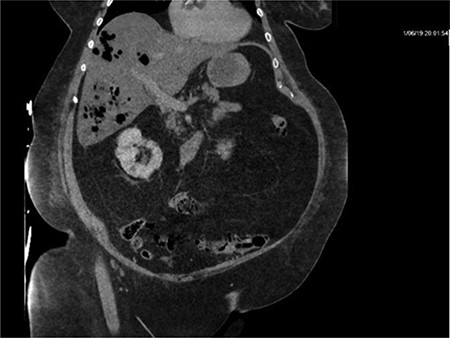

CT of the abdomen and pelvis with IV contrast was performed within 2 h of presentation. The scan showed “indeterminate, scattered ill-defined hypo-enhancing lesions in the liver with no acute etiology identified to explain the patient’s abdominal pain” (Figs 1, 3, 5). The remainder of the CT was unremarkable. Ultrasound (US) of the abdomen was negative. Because the CT and US did not identify an etiology for the patient’s abdominal pain, the working diagnosis at that time was an intestinal obstructive process.

CT with IV contrast taken at 0633 which shows ill defined, hypo-enhanced lesions of the liver.